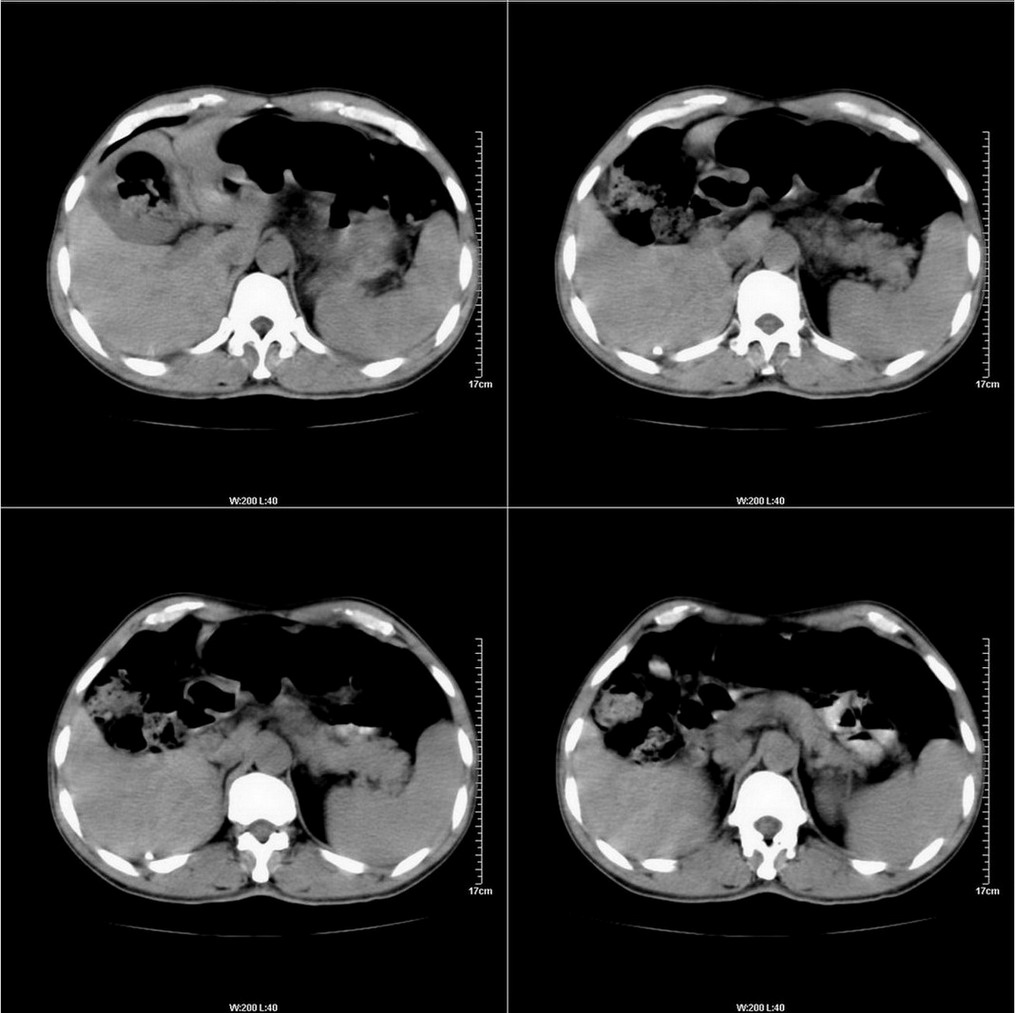

标题: CT14220:男性,59岁。腹部疼痛不适半年余。 [打印本页]

标题: CT14220:男性,59岁。腹部疼痛不适半年余。

考虑 胆囊病变.

建议结合胃镜或钡餐检查,考虑胃底贲门癌可能性大。

看着胆囊周围不舒服。